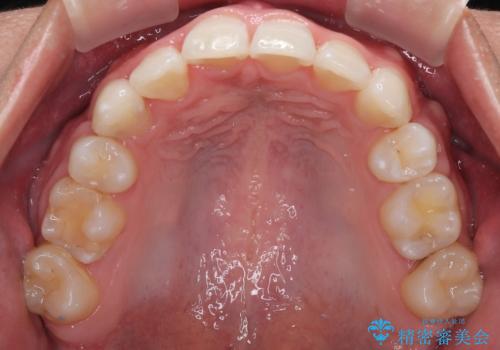

- 今回ご紹介するのは、

「全体的なデコボコ(叢生)」「上下の正中のずれ」 を主訴として来院された20代男性の患者様の症例です。

上下左右の第一小臼歯を抜歯して、矯正治療のための適切なスペースを確保する計画としました。

上顎左側第一大臼歯に齲蝕が認められたため、矯正治療終了後に 精度の高いセラミックインレー にて修復治療を行いました。